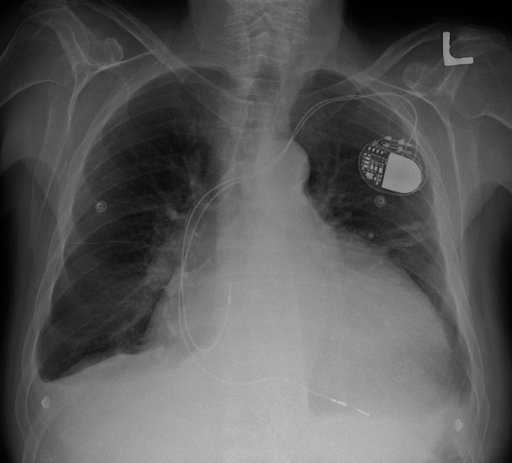

PA chest X-ray with mild cardiomegaly (CTR 0.55), LV prominence, clear lung fields